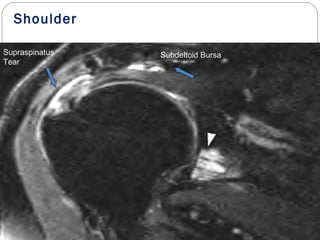

Shoulder

Supraspinatus

Tear

Subdeltoid Bursa